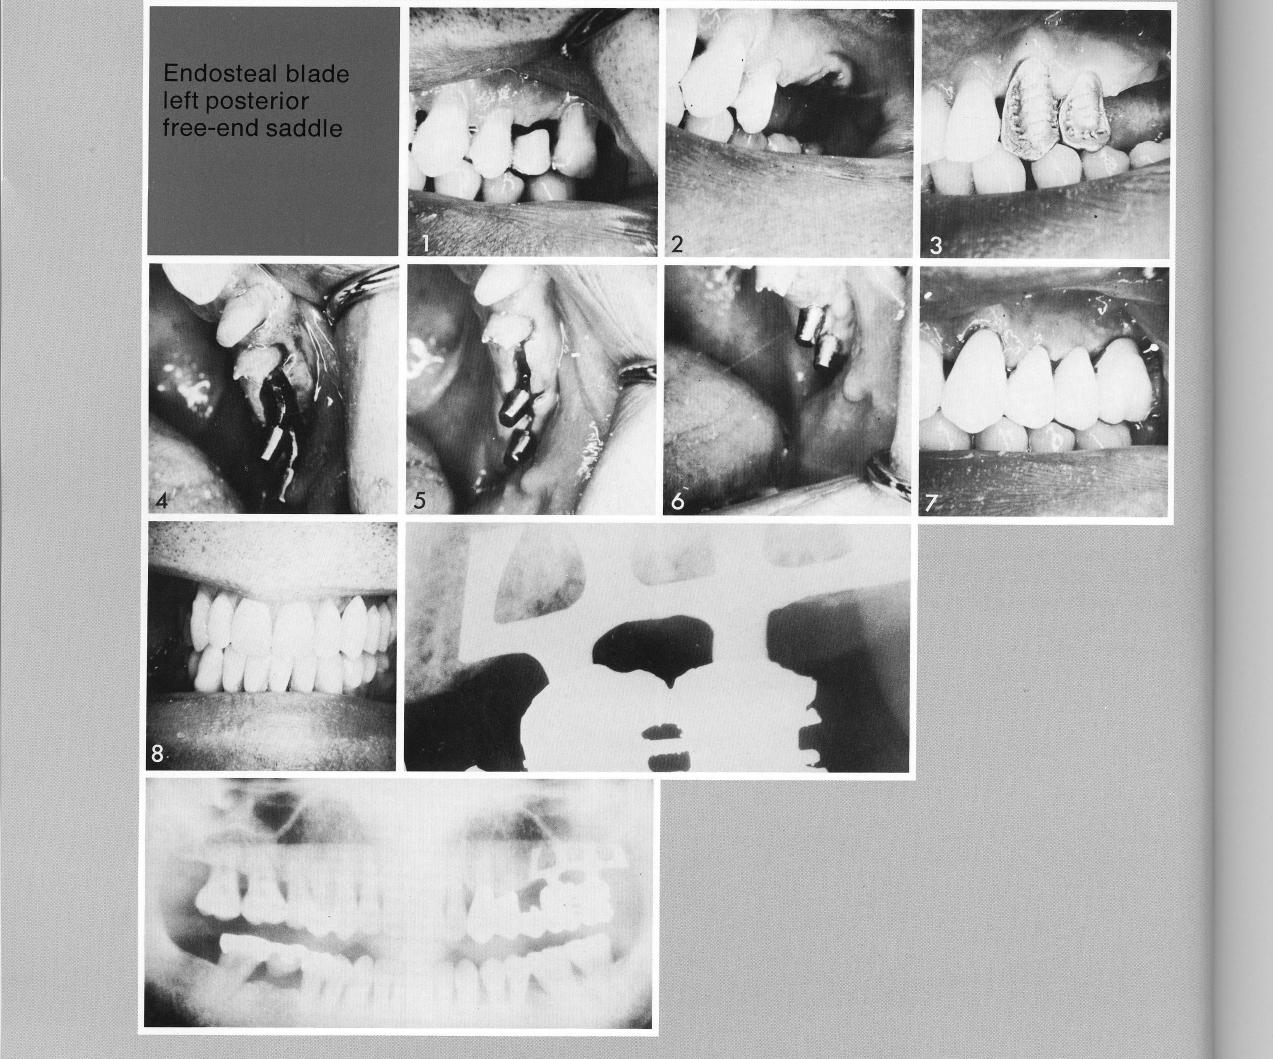

Posterior free end blade support

Unilateral examples of good bone under the sinus are not atypical, and constitute a good portion of the cases seen in young people. Here an extraction was necessary (1,2), and two teeth mesial to the span prepared for inclusion in the restoration (3). A double-posted bladevent was inserted (4,5), and an attractive partial restoration fashioned for the site (7,8).

1 Good maxillary bone under the sinus for implantation

2 A double posted maxillary bladevent implant inserted